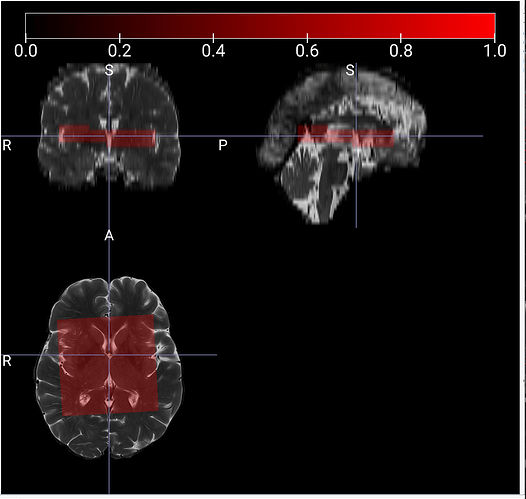

I’m afraid I’m still confused. In both your axial images, the brain and acquisition slab are angled in the same direction. They just appear to be flipped L-R (radiological vs. neurological convention). Could you open the image in a different image viewer like MRIcroGL, overlap the voxel mask, and show L-R, A-P, S-I labels?

This is how it looks

According to the image from the scanner, the upper left corner should appear higher, but in my printouts the upper left is higher. I also added the flipped (row-wise down) mask as an overlay (green). I think it should appear like this.